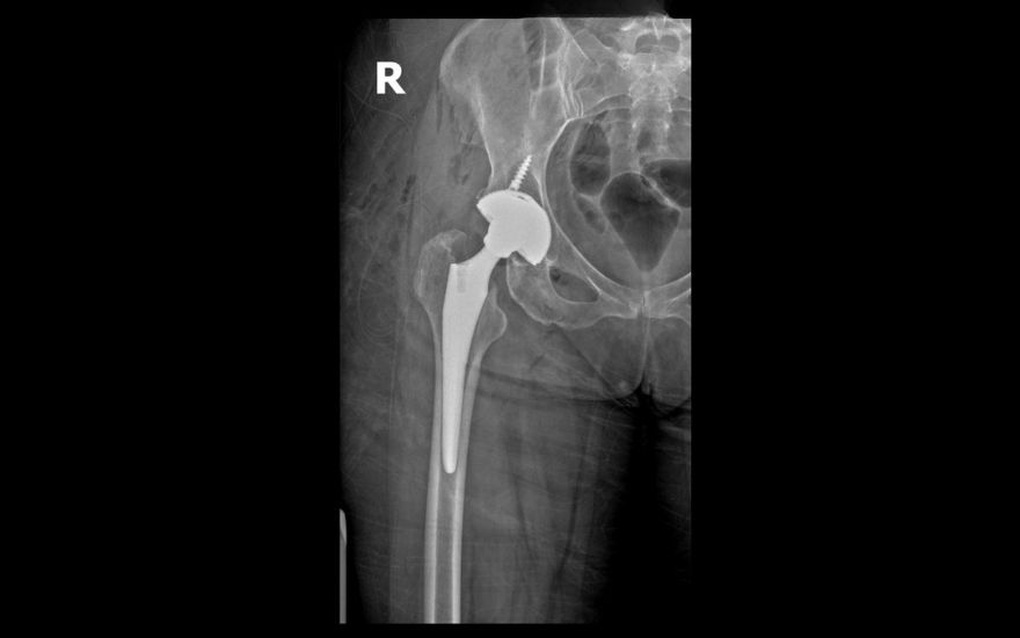

Radiographie de la hanche postopératoire du patient Ronit.

À l'hôpital général Hong Ngoc - Phuc Truong Minh, Mme Ronit a été examinée directement par le Dr Le Quang Huy, chef du service de chirurgie orthopédique traumatologique et de neurologie crânienne. Après une évaluation complète des symptômes et des résultats de la radiographie, le médecin a diagnostiqué une fracture fermée du col du fémur droit et a préconisé une arthroplastie totale de la hanche sans ciment, avec une prothèse à deux mouvements, afin de soulager la douleur et de restaurer la structure et la fonction motrice.

Le Dr Le Quang Huy a déclaré : « Dans ce cas précis, nous avons opté pour une prothèse de hanche utilisant la technique SuperPATH, qui présente de nombreux avantages : petite incision, intervention mini-invasive, absence de section des tendons, ce qui contribue à limiter les lésions des tissus mous, à réduire la douleur et à permettre la mobilisation dès le lendemain de l’opération. L’intervention utilise une prothèse de hanche à deux mouvements dotée d’une structure particulière composée de deux couches de têtes osseuses mobiles à l’intérieur de l’acétabulum, afin d’accroître l’amplitude des mouvements et la flexibilité de l’articulation et de réduire le risque de luxation postopératoire. »

Selon le Dr Le Quang Huy, la nouvelle génération de prothèses de hanche à deux mouvements est largement utilisée en Europe et présente de nombreux avantages par rapport aux prothèses conventionnelles. Cette prothèse est composée de deux couches de polyéthylène et de têtes fémorales en métal, ce qui permet d'accroître l'amplitude de mouvement de la hanche de 20 degrés, sa rotation de 25 degrés et sa flexion de 30 degrés.

Les deux têtes fémorales sont reliées par un mécanisme de verrouillage rapide, assurant la stabilité, une bonne mobilité et réduisant le risque de luxation postopératoire. Ainsi, les patients peuvent rapidement reprendre leurs activités quotidiennes, comme s'accroupir, faire du vélo ou croiser les jambes.

Après plus d'une heure, l'opération a été un succès et le col fémoral fracturé a été remplacé par une articulation artificielle haute résistance capable de supporter la charge, permettant au patient de conserver une mobilité à long terme.